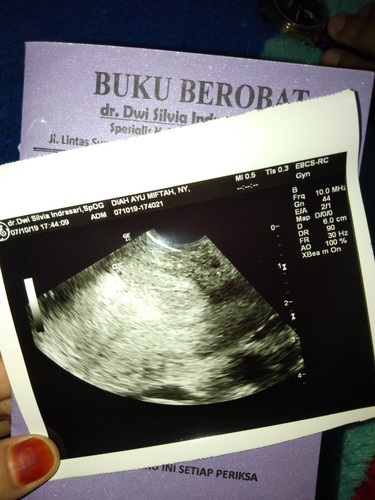

HASIL USG ±4week

Tempo hari saya USG untuk memastikan hasilnya Positif atau Negatif. Alhamdulillah kata dokternya Positif dan perkiraan umur janin 4week. Tapi baru berupa Titik kecik. Apakah ibu² ada juga yang seperti saya? Baru berupa titik kecil seperti itu